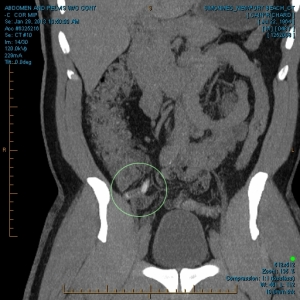

“My family and I have been the subjects of Government funded human research and/or hate crimes. These crimes are being covered-up by using the words National Security. The fact that my two minor children have the same and/or similar devices in their little bodies speaks for themselves. My sons were ages 3 and 4 when the discoveries took place. Their x-rays, blood & urine analysis present the true facts. The devices can only be introduced into the body, while being in a medical facility. All three of us were patient of the same defendant hospital.

“The CD-ROM from CCAI depicts the same images that are attached. I will bring the 01/03/2012 Simonmed Imaging CT scan which also depict foreign objets in the heart and chest.”

“Please take a look at both X-rays. Superimpose the foreign objects AKA EKG clamps and you will find that they are the same devices. when have you ever seen an EKG clamp place sideways in the abdomen? Both x-rays have been confirmed by Radiologist Louis Teresi as having foreign body reactions in the abdomen, right and left flanks.

“The obvious implant in the 2012 x-ray stands out from the others, because it at the time had not embedded into my flesh (heart).”